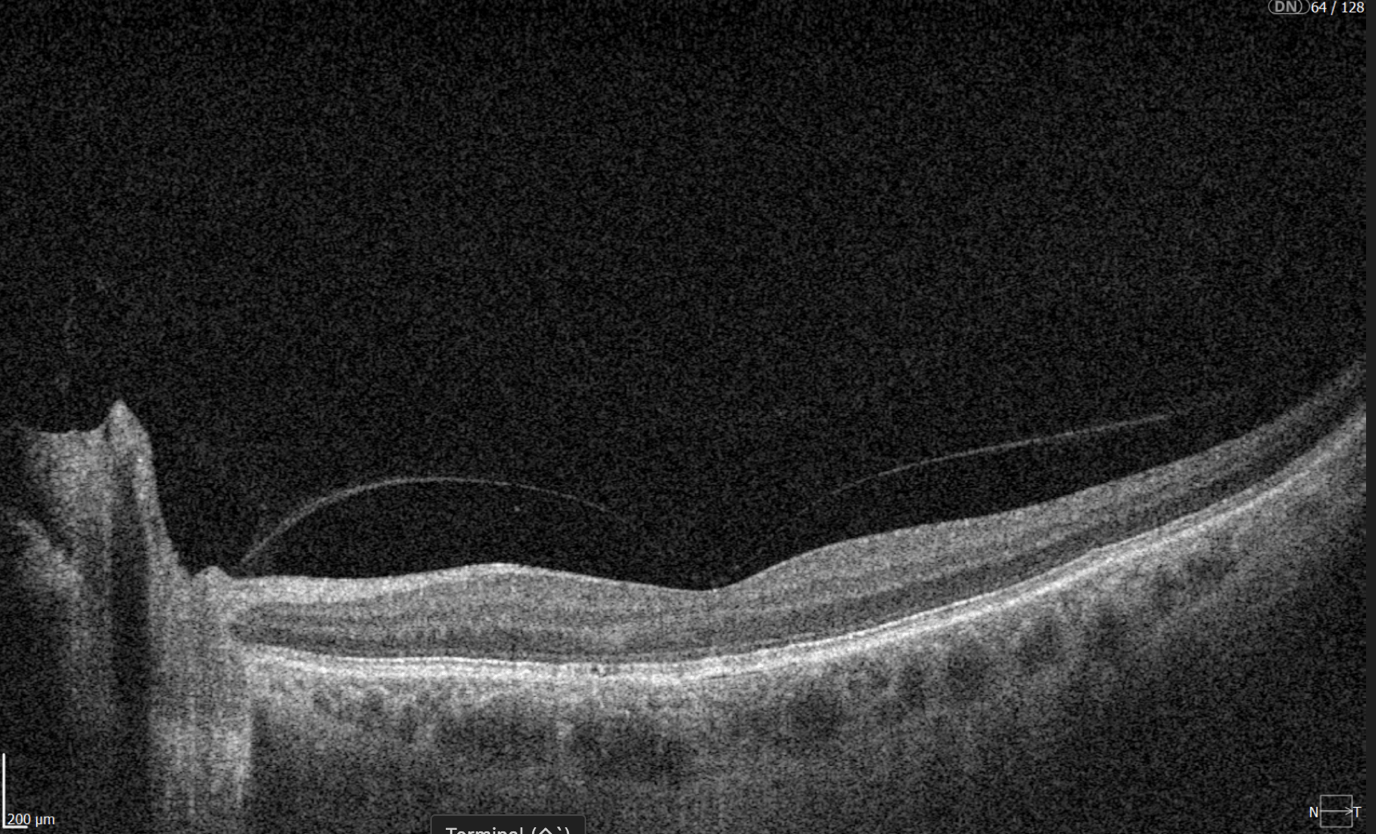

Advanced findings

OCT can also reveal proliferative changes and tractional zones, which may progress to tractional retinal detachment.OCTA insights

Diabetic retinopathy (hyperreflective foci, microaneurysms, destruction of the ellipsoid zone and RPE), diabetic macular edema (neuroepithelial swelling, intraretinal cystic cavities), epiretinal membrane. Monitoring of diabetic retinopathy progression

Diabetic retinopathy (hyperreflective foci, hard exudates, destruction of the ellipsoid zone and RPE, disorganisation of the retinal inner layers (DRIL)), Diabetic macular edema (neuroepithelial swelling, intraretinal cystic cavities), subretinal fluid. The appearance of these OCT features should prompt clinicians to reconsider therapy, whether by switching anti-VEGF agents, introducing steroids, using combination therapy, or referring patients for surgical evaluation when traction is present.

Diabetic retinopathy (hyperreflective foci, hard exudates, destruction of the RPE), Diabetic macular edema (neuroepithelial swelling, intraretinal cystic cavities), subretinal fluid. What is the best treatment for diabetic retinopathy?